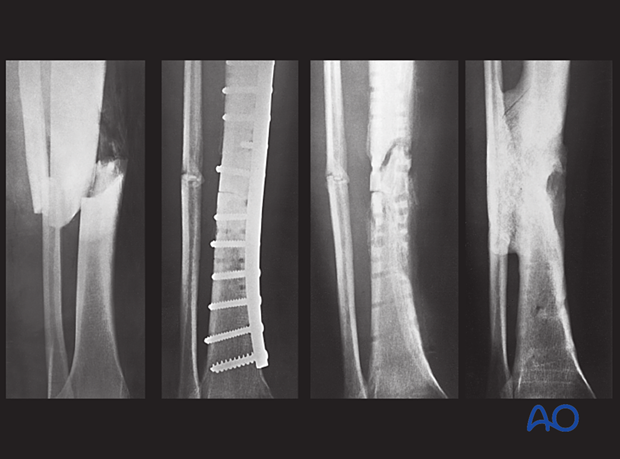

This patient had an acute fracture, necessitating internal fixation. However, a late infection occurred. X-rays and subsequent debridement revealed an ununited fracture with minimal callus formation. Intercalary necrotic bone was debrided. The fracture was stabilized with an external fixator.

Appropriate antibiotics were administered. Bone graft was then placed in the fracture defect and between the tibia and fibula above and below the fracture. This combination of treatments improved both the biology and stability of the atrophic nonunion. Delayed healing occurred with a satisfactory outcome.